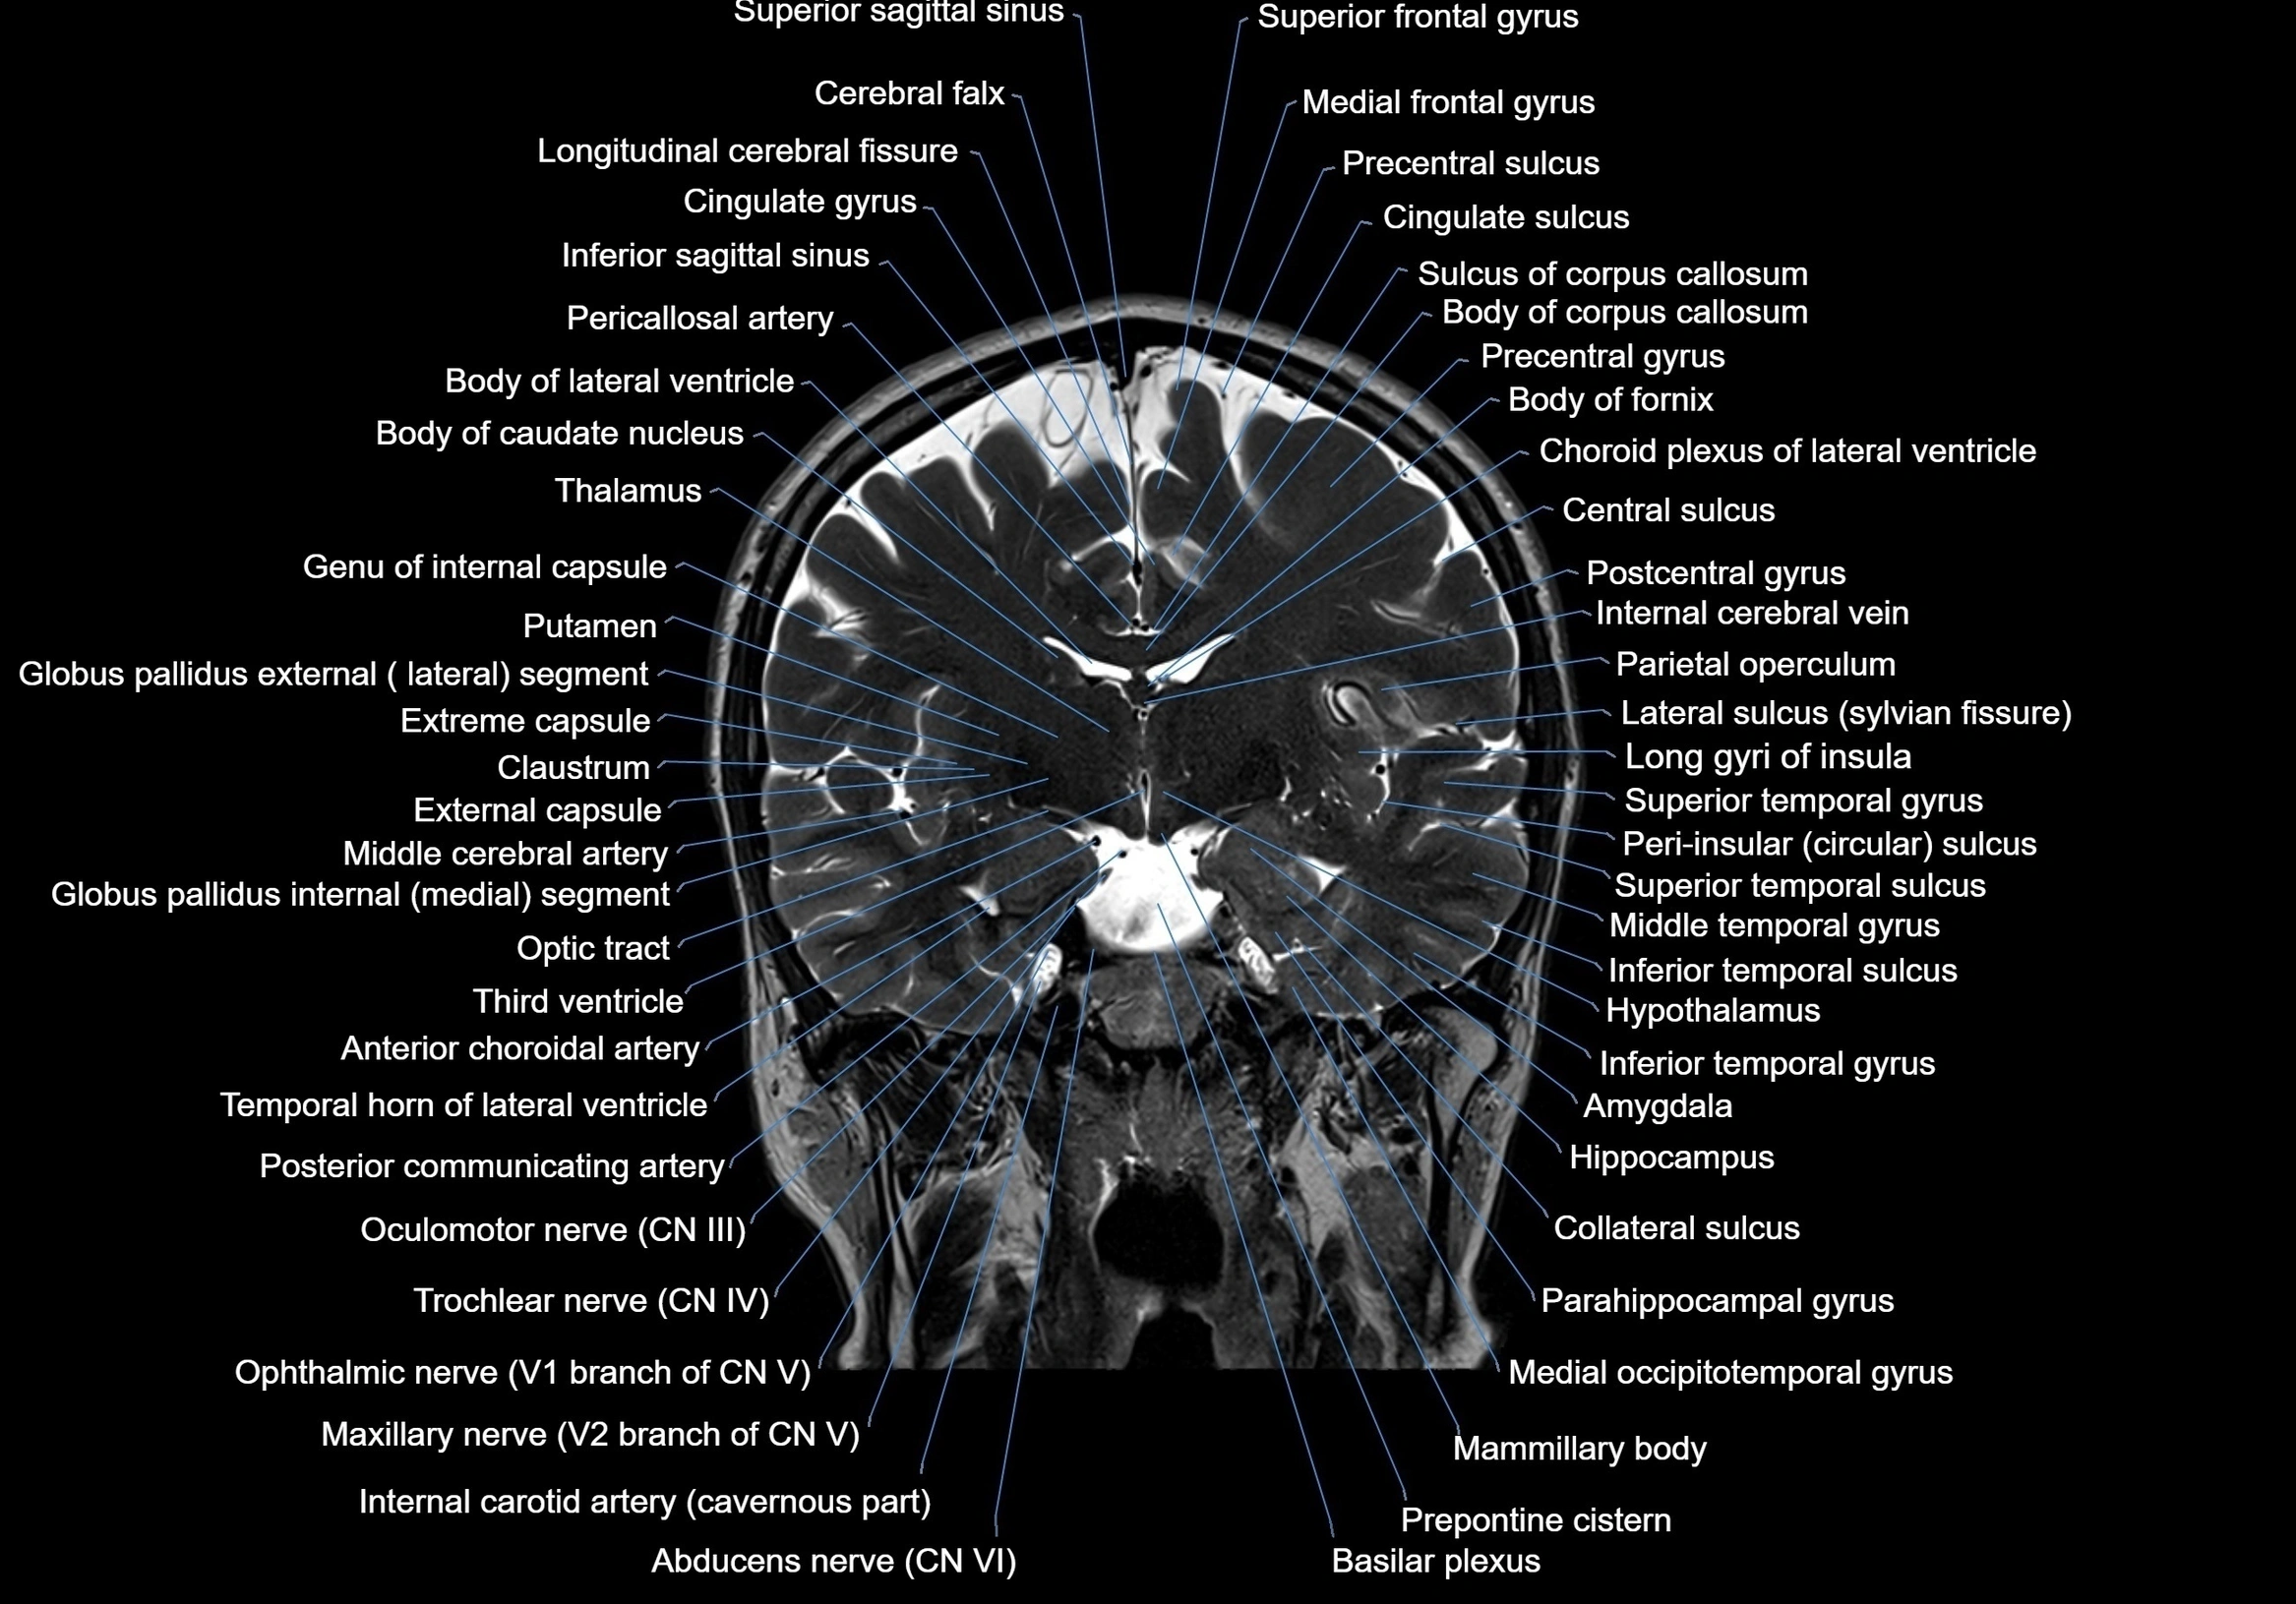

MRI images